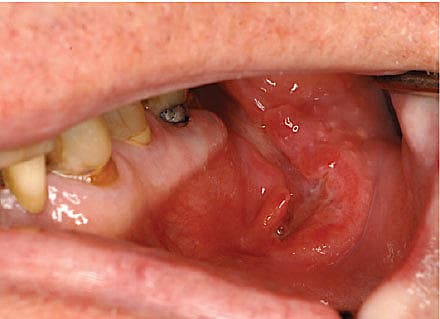

En 80-årig mand, der havde monoclonal gammopathy of undetermined significance, gennemgik i juni måned ekstraktion af en kindtand i venstre side af undermunden hos egen tandlæge. Grundet kompromitteret sårheling, spredning af såret til indersiden af gingiva bag bagerste molar samt smerter blev patienten henvist til biopsi på en øre-næse-hals-afdeling. Initialt var der mistanke om oral manifestation af myelomatose, men histologisvaret viste, at det drejede sig om EBV-infektion. Ved kontrol hos en kæbekirurg i oktober blev forandringen i kindslimhinden genfundet, og der var mistanke om et karcinom i mundhulen. Ud fra biopsier fra den orale forandring konkluderede man, at der var tale om kronisk ulcus uden tegn til malignitet. Patienten blev nu henvist til vurdering på en plastikkirurgisk afdeling, hvor man foretog excision in toto af den ca. 1 × 2 cm store forandring. En efterfølgende ultralydskanning af halsen viste flere bilaterale små lymfeknuder (≤ 1 cm i diameter) med normal morfologi langs karrene og en 1,5 cm i diameter stor suspekt lymfeknude på højre side af halsen. En finnålsbiopsi fra lymfeknuden var inkonklusiv, og en biopsi fra venstre tonsilleje viste uspecifik reaktiv

forandring. Vha. vævsprøverne fra kindslimhinden kunne man fastslå, at der var tale om EBV-LPD, hvilket var foreneligt med T-lymfocytdysfunktion, med »obs.« iatrogen eller aldersbetinget immunsuppression. Patienten oplevede herefter spontan bedring, hvorfor man afventede situationen under ambulant kontrol.